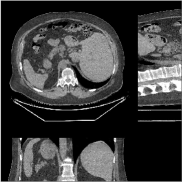

Fig.Β 7 shows the reconstructions (shown for the central axial plane in the 3D volume) for FDK (provided by GE Healthcare), PWLS-EP (corresponds to Fig.Β 8(a)), and PWLS-ULTRA with (corresponds to Fig.Β 9(a)). The PWLS-ULTRA reconstruction has lower artifacts and noise. Moreover, the image features and edges are better reconstructed by PWLS-ULTRA than by PWLS-EP or FDK.

Fig.Β 8 shows the reconstructions (shown for the central axial, sagittal, and coronal planes in the 3D volume) for PWLS-EP with different regularization strengths , denoted as a multiplicative factor of the parameter value in Fig.Β 7. Fig.Β 9 shows the reconstructions for PWLS-ULTRA (with patch-based weights) with different parameter combinations. For the sagittal and coronal planes, we show the central out of axial slices. Larger regularization strengths would achieve more noise reduction but simultaneously lower spatial resolution in PWLS-EP and PWLS-ULTRA, e.g., compare Fig.Β 8 and Figs.Β 9(a) and (d). Larger values of would achieve lower sparsities and more noise reduction but potentially oversmooth the image, e.g., compare Figs.Β 9(c) and (d). Small values of may introduce additional spurious noise in the PWLS-ULTRA reconstruction (compare Figs.Β 9(a) and (b)). Fig.Β 11 shows profiles of chest reconstructions (plotted from the central axial slice) for the PWLS-EP and PWLS-ULTRA methods. The profile locations are shown in green lines in Fig.Β 7. Both PWLS-EP with regularization strength X and PWLS-ULTRA (with patch-based weights) in Fig.Β 9(a) have lower noise than the PWLS-EP with regularization strength X. Though the spatial resolution of PWLS-EP with regularization strength X is close to PWLS-ULTRA in the selected soft-tissue regions, PWLS-ULTRA reconstructs bone and spine areas with higher resolution, and preserves small features better (compare the zoomed-in areas in Fig.Β 8 and Fig.Β 9).